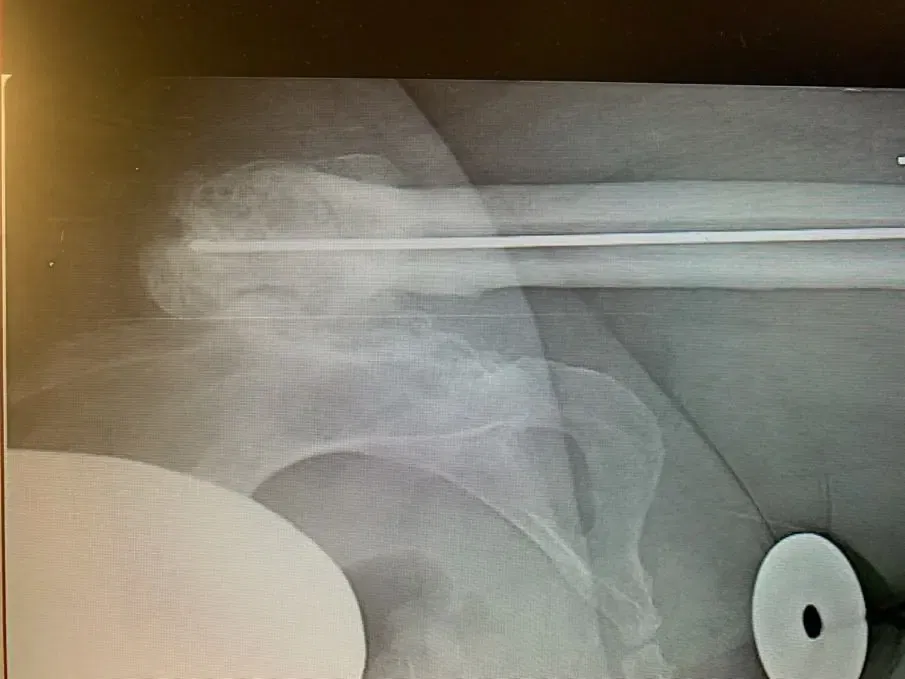

Plain film radiographs revealed a significantly arthritic hip with dysplastic features on both sides of the joint. Her contralateral hip revealed similar findings, but of lesser severity.